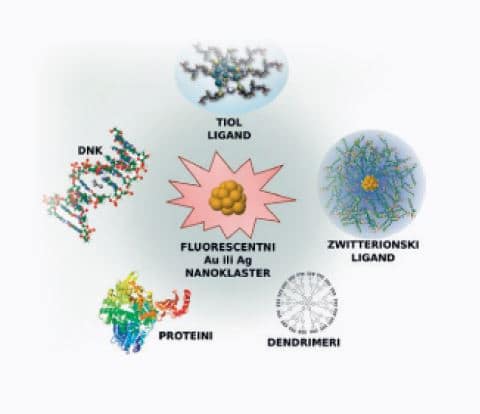

- Biosenzorika superiorne detekcije temelji se na metalnim nanoklasterima zaštićenima biološkim molekulama (novoj klasi nelinearnih fluorofora) koji dozvoljavaju duboku penetraciju u tkivo te direktno oslikavanje živih stanica za ranu medicinsku dijagnostiku.

- Experimentalni dio: Dr. Rodolphe Antoine i Dr. Philippe Dugourd (Université Claude Bernard Lyon 1, CNRS, Lyon, France)

Oksidacija proteina jedan je od najboljih markera starenja i upalnih procesa. Metalni nanoklasteri: Novi detektori karbonilacije proteina 2D-oxyDIGE gel proteina ljudske plazme.

Glutation reduktaza, modelni protein koji koristimo za razvoj detekcije proteinske karbonilacije uz pomoć metalnih nanoklastera.

Razvoj i primjena metalnih nanoklastera za detekciju i kvantifikaciju proteinske karbonilacije in vitro i in vivo Suradnja s prof. Vlastom Bonačić-Koutecký i dr. Rodolphe Antoine (Université Claude Bernard Lyon 1, CNRS, Lyon, France)

Karbonilacija proteina može se detektirati i mjeriti pomoću 2D-oxyDIGE metode koja koristi specifičnu fluorescentnu probu vezanu na hidrazid koji reagira s karbonilnom skupinom.

Kao model koristi se protein SOD1 koji je vezan uz pojavu teške neurodegenerativne bolesti amiotrofične lateralne skleroze (ALS). Odabrani su mutanti SOD1 za koje se pretpostavlja da će imati veću osjetljivost na karbonilaciju i stvaranje agregata.

Kako bi se poboljšala specifičnost i osjetljivost tehnike, razvijaju se nanoklasteri koji zamjenjuju te ci-hidrazidne boje.